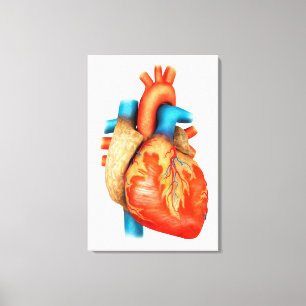

Lienzo Imagen de la radiografía de órganos internos con

Precio 218,00 €